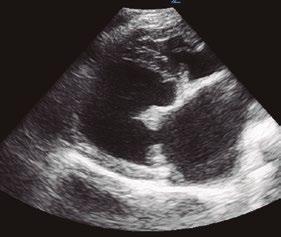

Utilidad clínica de la ecografía pulmonar y cardiaca en urgencias